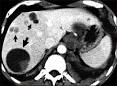

Equinococo. (Del griego echinos, erizo, y kokkos, grano). Tenia que vive en el intestino del perro y cuyo huevo, ingerido por el hombre con sus alimentos, da lugar a un embrión hexacanto. Este último, después de haber atravesado las paredes del intestino, se fija en un órgano, generalmente el hígado, en donde produce al desarrollarse el quiste hydatídico.